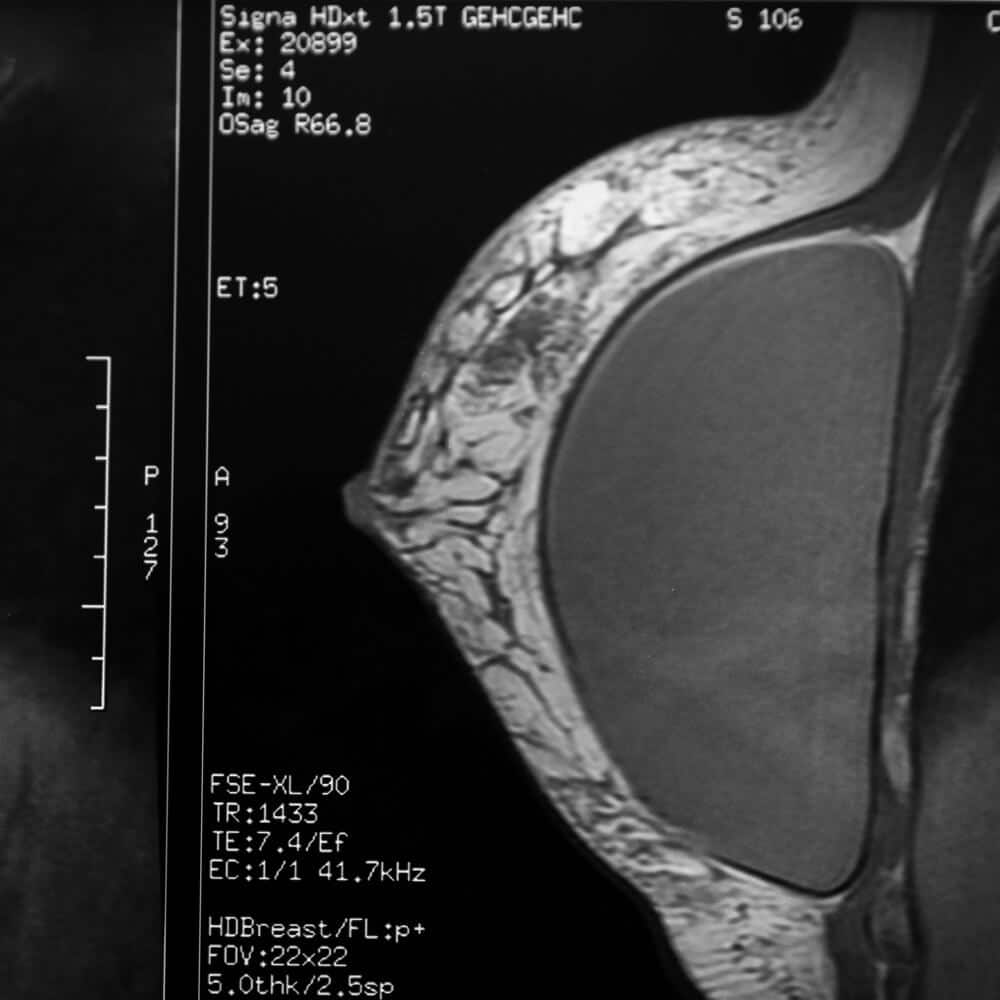

Our Breast Implant MRI is a focused scan used to evaluate the integrity of breast implants and the surrounding capsule. It is performed without contrast and can help detect signs of implant rupture in a non-invasive way.

This MRI protocol is tailored to evaluate silicone breast implants and the fibrous capsule around them. It is not a general breast cancer screening test, but a targeted tool to help assess implant integrity.